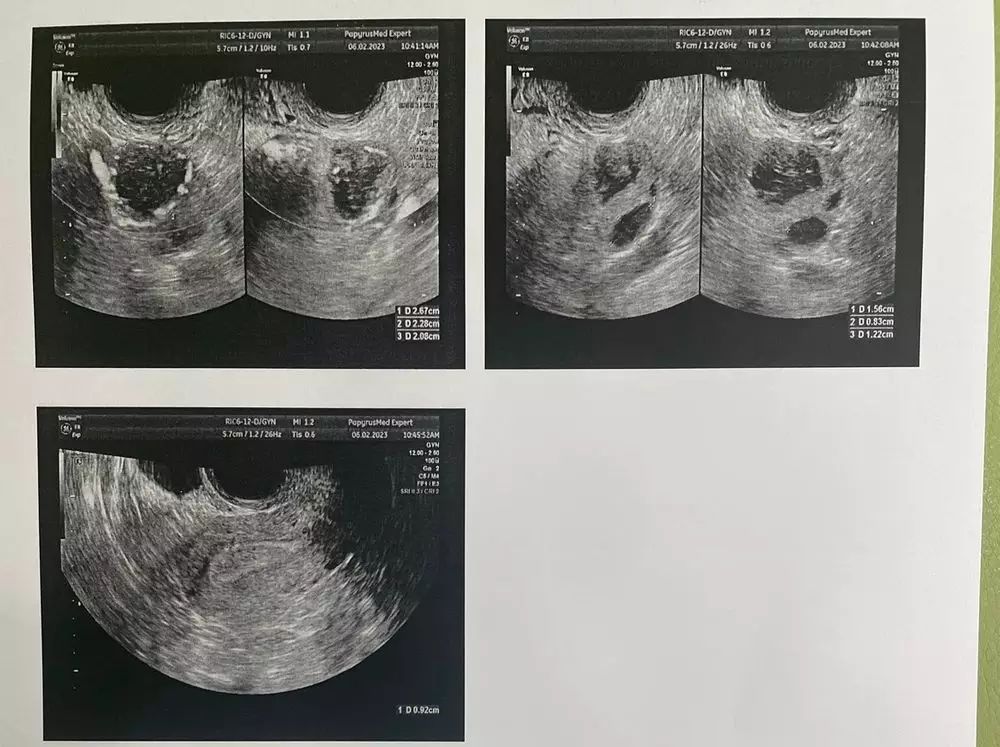

Всем привет.Сходила на узи.Врач не уверен,произошла овуляция или нет.. если была не давно,то не успело образоваться желтое тело.У кого нибудь было похожее?

Что в итоге было киста или желтое тело.

Овуляция по ощущениям была с субботы/на воскресенье.